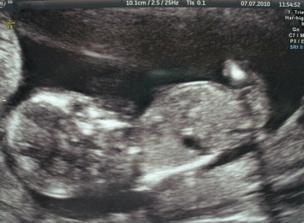

7. července 13+3tt - NT screening - OK, termín porodu 9. ledna 2011.

- 1. poradna, léky sníženy na polovinu a postupně odebírány do další kontroly.

- 59kg (+6kg)